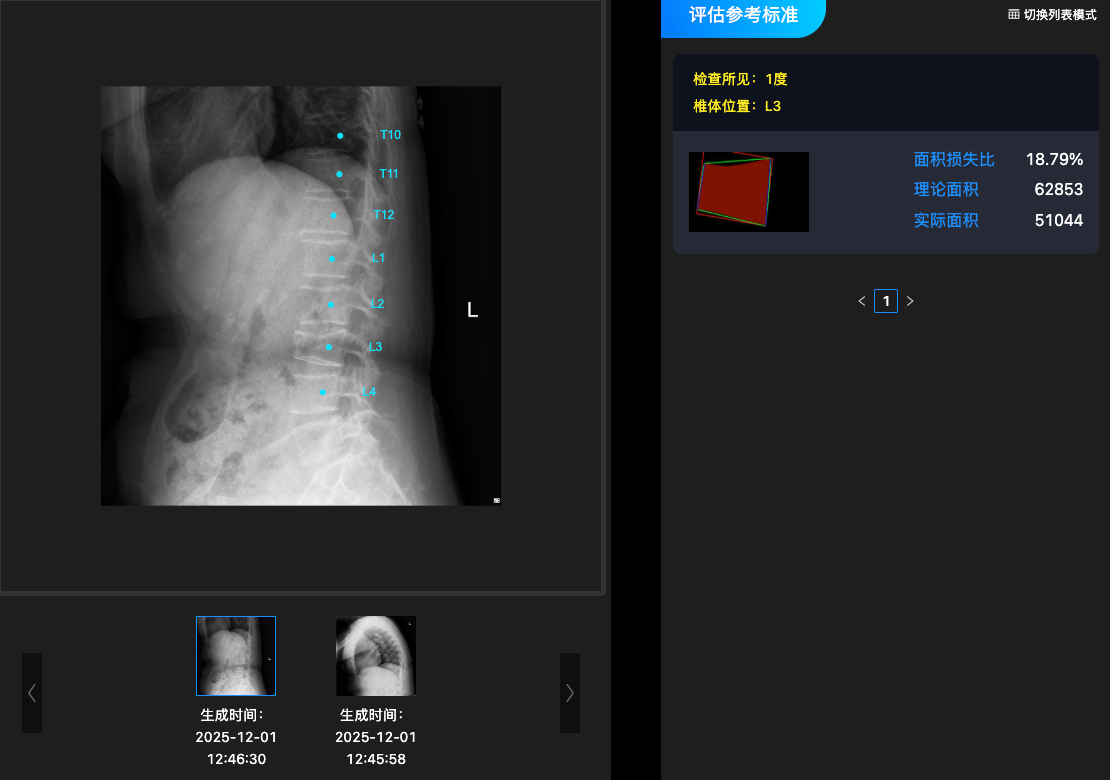

椎体X射线影像处理软件(基于X线片)

全球首个基于X线侧位片的AI影像智能识别系统,通过图像深度学习算法实现椎体自动定位与骨折智能分度识别,显著提升骨质疏松性椎体骨折的影像评估效率和诊断准确性,并已获上海市第二类创新医疗器械认证。